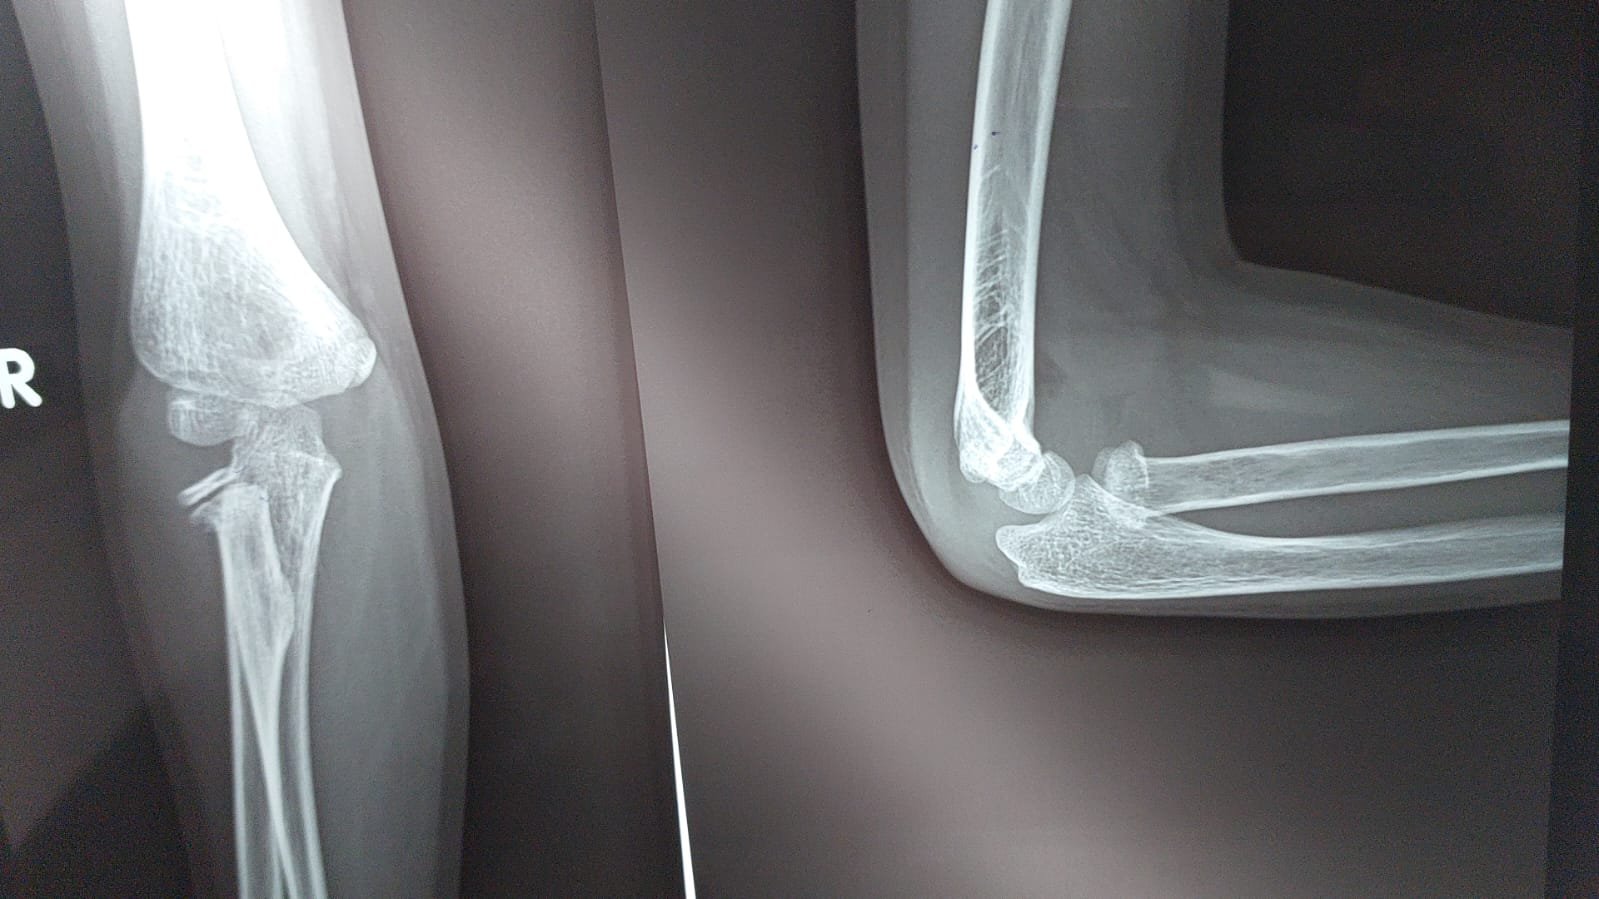

Radial Head & Neck Fractures  (Adults & Paediatrics)

Overview — Radial Head Fractures

Radial head fractures are the most common fractures about the elbow in adults, accounting for approximately 33% of all elbow fractures. They occur most commonly from a fall onto an outstretched hand (FOOSH), during which axial compression transmits force from the wrist through the forearm to the radiocapitellar joint, fracturing the radial head as it impacts the capitellum. The Mason classification (1954), modified by Johnston (1962), Broberg and Morrey (1987), and Hotchkiss (1997), is the universal system for describing radial head fracture morphology and guides management — from conservative treatment for simple undisplaced fractures to arthroplasty for severely comminuted fractures.